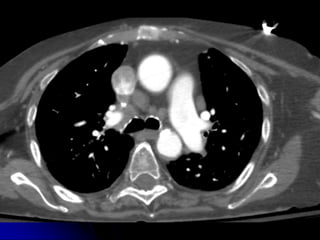

INCIDENTAL

FINDINGS &

COMORBIDITIES